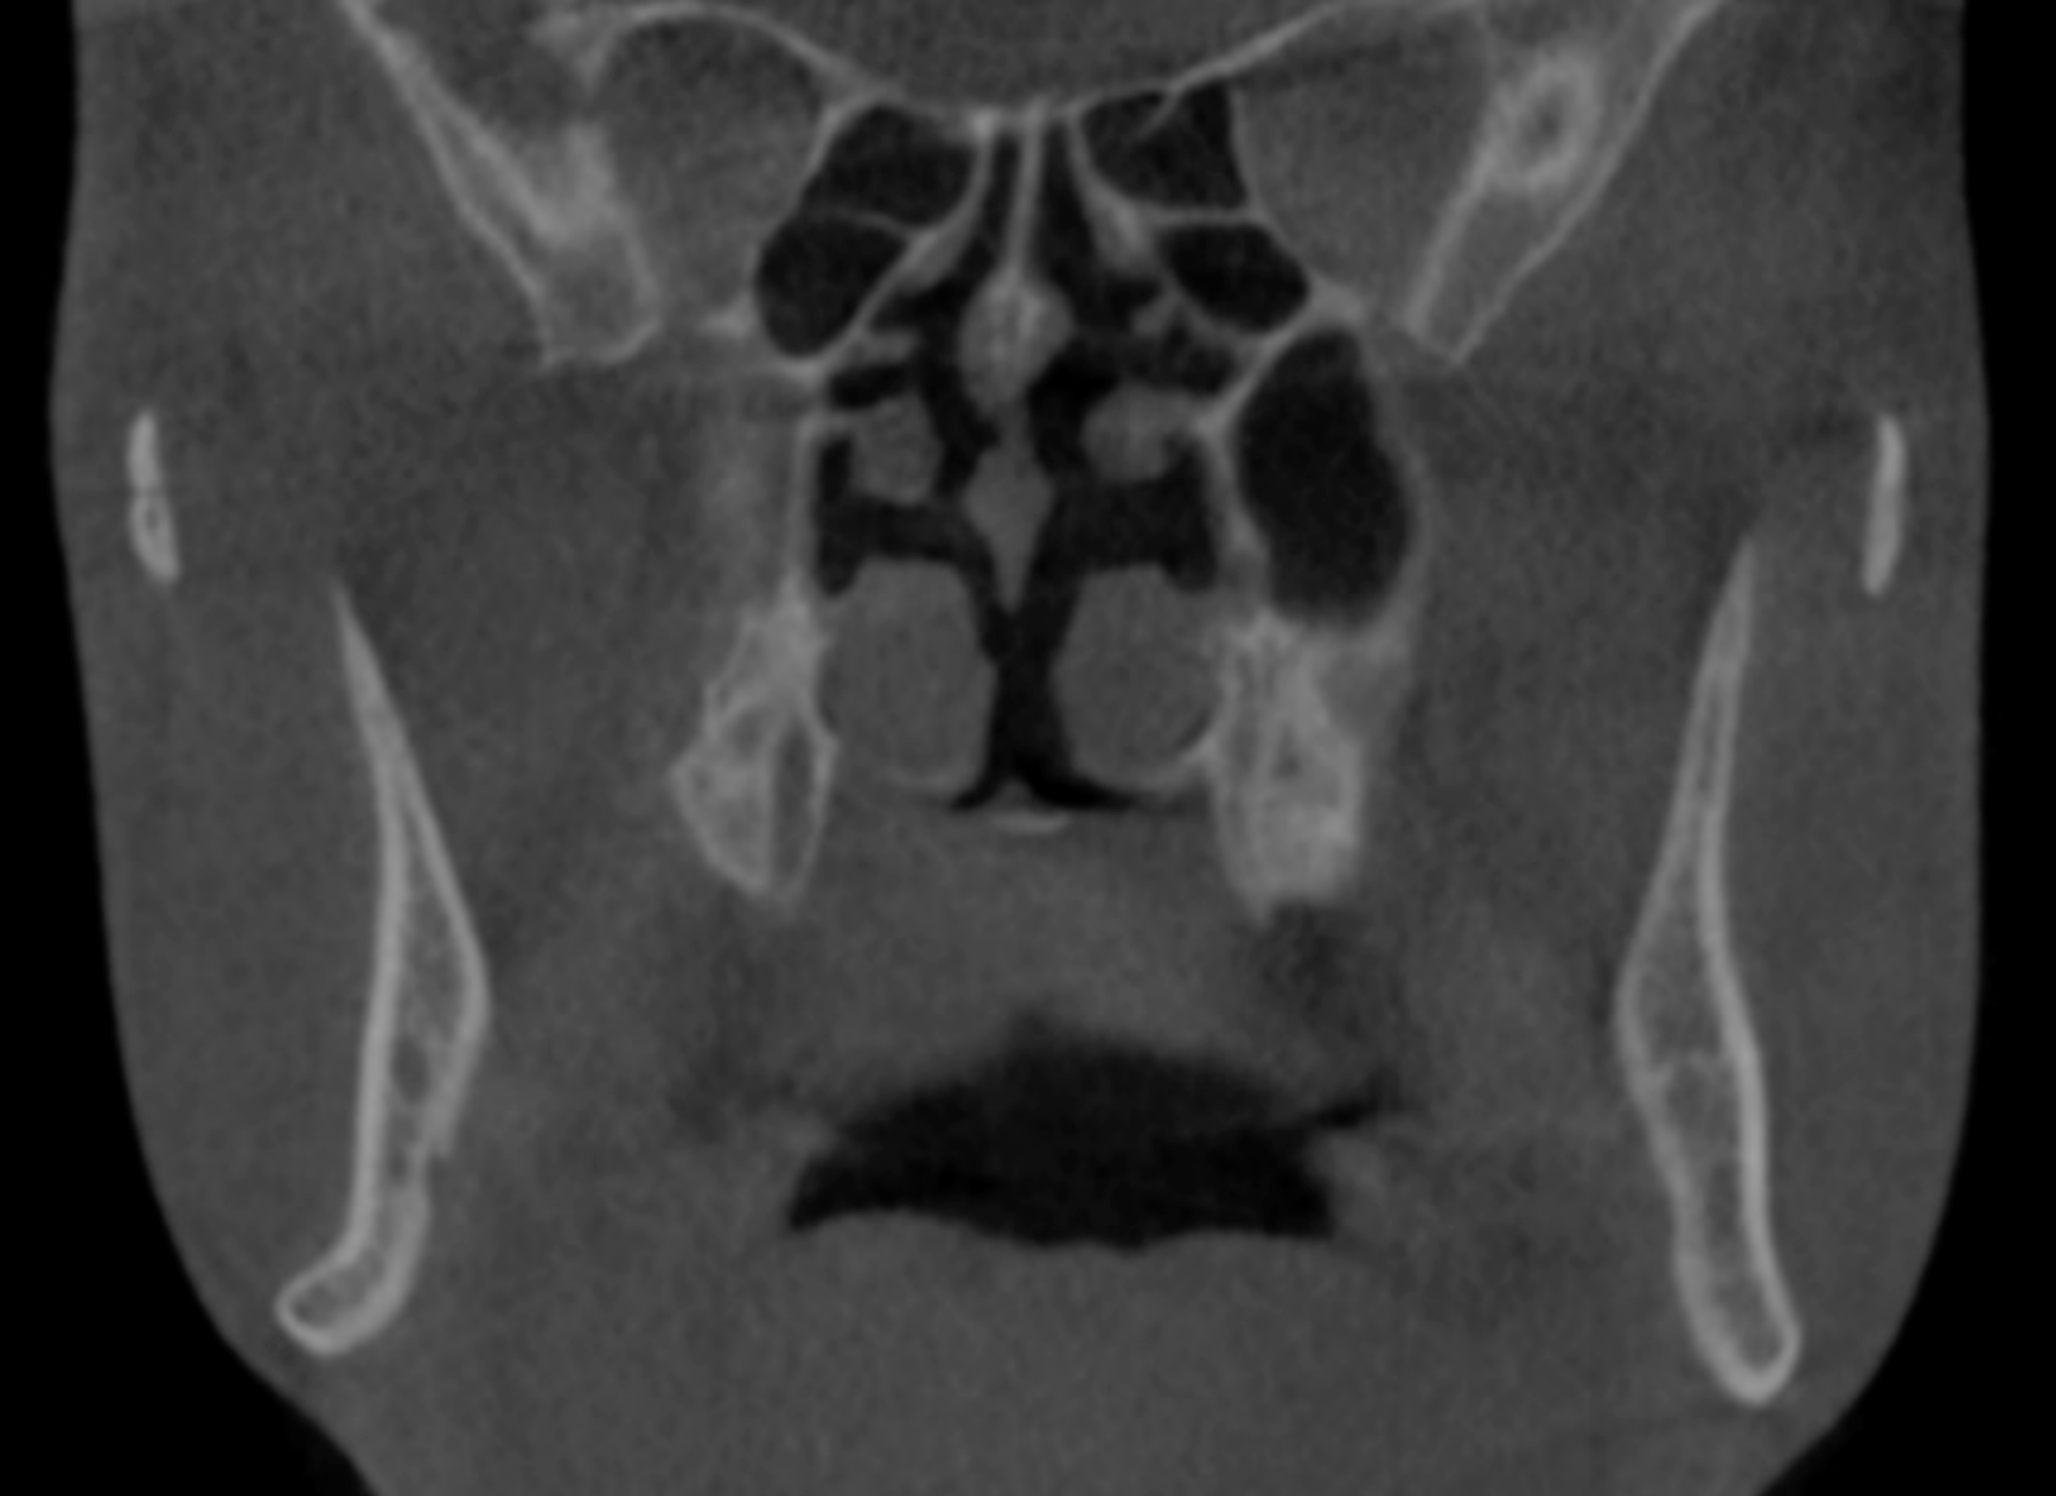

Fig. 1

A CBCT coronal cut showing the thin mandibular rami, rolling out of the inferior mandibular border, and the IAN proximity to the buccal cortex

The study was registered on ClinicalTrials.gov under the registry number NCT05397002. It adhered to the Declaration of Helsinki on medical research ethics and received approval from the Institutional Research Ethics Committee of the Faculty of Dentistry, Cairo University (IRB number: 151020). This prospective, single-center case series included 20 patients consecutively recruited from the outpatient clinic of the Department of Oral and Maxillofacial Surgery, Faculty of Dentistry, Cairo University. Patient recruitment began in October 2020 and continued until April 2022. The intervention phase was conducted from December 2020 to April 2022, with follow-up extending from December 2020 to April 2023. Data collection was carried out throughout the study duration, concluding in May 2023. Patients were selected according to the following inclusion criteria: (1) Adult patients complaining of skeletal class III malocclusion requiring mono-maxillary or bi-maxillary surgical intervention; (2) CBCT examination revealed anatomical hindrances that interfere with the application of BSSO indicating the application of the currently modified intraoral ILRO osteotomy (thin mandibular rami with minimal or no medullary bone, inferior alveolar nerve proximity to the buccal cortex along the length of the BSSO cuts, lateral bending of the inferior mandibular border at molar angle region, high mandibular foramen, inferiorly seated IAN canal and extensive distal interferences) (Fig. 1) and (Fig. 2). Patients with previous extensive jaw surgery, mandibular pathological lesions, or temporomandibular joint dysfunction were excluded from the study.